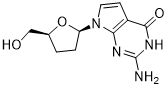

馬鞍山致研生物醫(yī)藥科技有限公司成立于馬鞍山市鄭浦港新區(qū)現(xiàn)代產(chǎn)業(yè)園。公司專(zhuān)注于生物小分子、醫(yī)藥中間體相關(guān)產(chǎn)品的研發(fā)和生產(chǎn),產(chǎn)品主要包括DNA亞磷酰胺單體、RNA亞磷酰胺單體、特殊單體以及按照客戶(hù)要求定制的RNA和DNA,并且公司提供定制合成等方面的研究服...

馬鞍山致研生物醫(yī)藥科技有限公司成立于馬鞍山市鄭浦港新區(qū)現(xiàn)代產(chǎn)業(yè)園。公司專(zhuān)注于生物小分子、醫(yī)藥中間體相關(guān)產(chǎn)品的研發(fā)和生產(chǎn),產(chǎn)品主要包括DNA亞磷酰胺單體、RNA亞磷酰胺單體、特殊單體以及按照客戶(hù)要求定制的RNA和DNA,并且公司提供定制合成等方面的研究服...